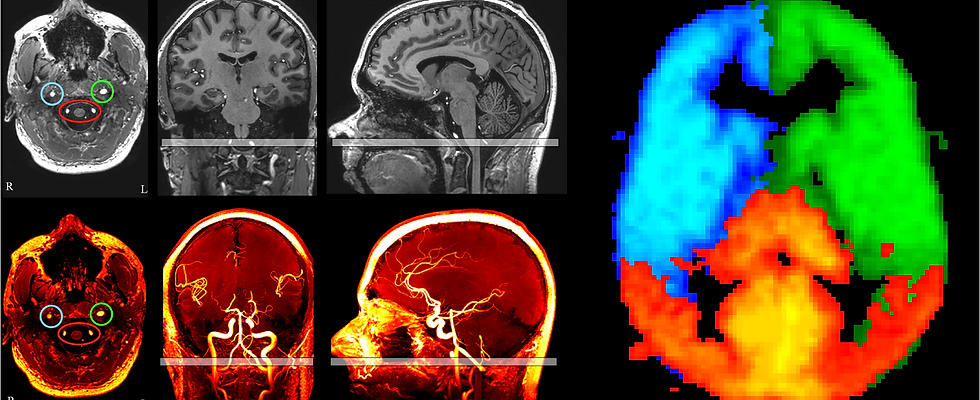

Our current work in cerebrovascular disease focuses on moyamoya vasculopathy, a condition where the blood vessels within the brain narrow in the absence of typical atherosclerosis. We study how the brain compensates for this condition using new magnetic resonance imaging assessments of cerebrovascular reserve capacity, perfusion, and oxygen extraction, and how this information can be used to triage patients for vascular surgeries.

More specifically, moyamoya disease (MMD) is a severe cerebrovascular condition with unknown cause and confers a high risk of stroke; although historically observed in individuals of East Asian ancestry, MMD is now being reported with increasing frequency in North America over a broader range of races and ethnicities. Stroke risk can be reduced when surgical revascularization procedures are performed, however, surgical response and disease trajectory can be highly variable, especially in the increasingly recognized North American phenotype. This work is focused on using novel neuroimaging methods, in combination with assessments of traditional stroke risk factors, at two of the largest MMD treatment centers to identify personalized signatures of brain tissue health that can be used to portend stroke risk, with the long-term goal of using this information to triage patients for appropriate and personalized surgical revascularization procedures.